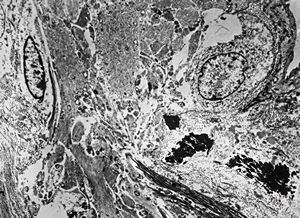

rabbit spinal cord trauma

rabbit spinal cord trauma